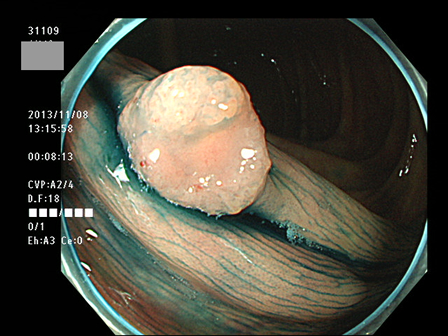

上記100名より抽出した平坦・陥凹型腺腫(=癌化の危険が高いが見落としやすい病変)の内視鏡写真